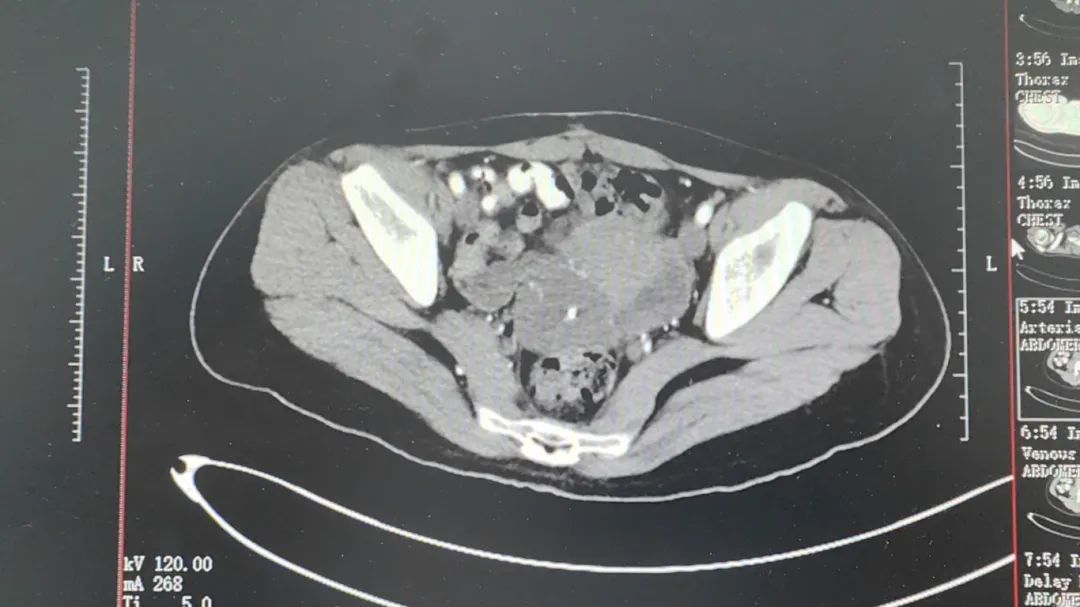

入院檢查發(fā)現(xiàn),小丹的子宮右后方囊性占位,與子宮、直腸、右側附件分界不清,從影像學的角度來看,有良性的可能。但不幸的是,術中冰凍結果為惡性。為此,我院專家決定為她采用冷凍消融+瘤內(nèi)注射術,既避免開刀,又可通過冷凍探針的冰球直接接觸腫瘤病變,減輕部分腫瘤負荷,延緩腫瘤進展,也起到了鎮(zhèn)痛的效果。